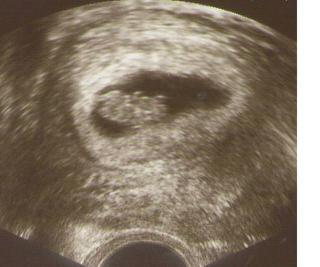

baby trosku ma desi to, ze v prvy den 6-teho tyzdna mi na sono doktor videl iba ten zltkovy obal ale ziadny plod vnutri, ani akciu srdiecka a vam niektorym to uz bolo vidiet, je to normalne?a objednal ma na dalsiu kontrolu az v septembri ked uz budem v 10 tt, aby som prisla na tie geneticke testy, nemal ma objednat este skor, aby zistil na sono, ci sa tam ukazal uz aj plod a srdiecko? dost sa bojim, lebo sam mi povedal, ze sa nemusi este vyvinut ten plod a mozem spontalne potratit, to kvoli tym kiahnam.....a volat mu tam a sama sa hlasit na sono ked nemam ziadne krvacanie ani ine problemy, mi je zasa blbe...aby som nesirila paniku...

@briketa, ja som tie sny mala dva krát po tom, ako sme rozoberali dvojčatá v rodine: u nás mamina sestra (jedno dvojča zomrelo) a u muža súrodenci ( jedno sa narodilo mŕtve, jedno žilo deň) . Takže celú noc sa mi snívalo, že nám hrozia dvojčatá - a kto vie, ako by to dopadlo. To bol teda sen... Samozrejme, ak by som čakala dve, po prvotnom šoku - ten priznávam 😲 by som sa na to pozerala inak, zdravotníctvo je o kus ďalej, ale predsa mi dnes odľahlo, keď som dnes videla plávať len jednu rybičku 🙂

baby, mam prvu fotecku, kuknite sa do mojho albumu "Krpec" 🙂)))